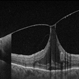

- maculoschisis, foveoschisis

Optical coherence tomography system

Zeiss Cirrus 6000 - Description

- HD 6x6 OCT-Angiography Structural View of the Deep Inner Retina